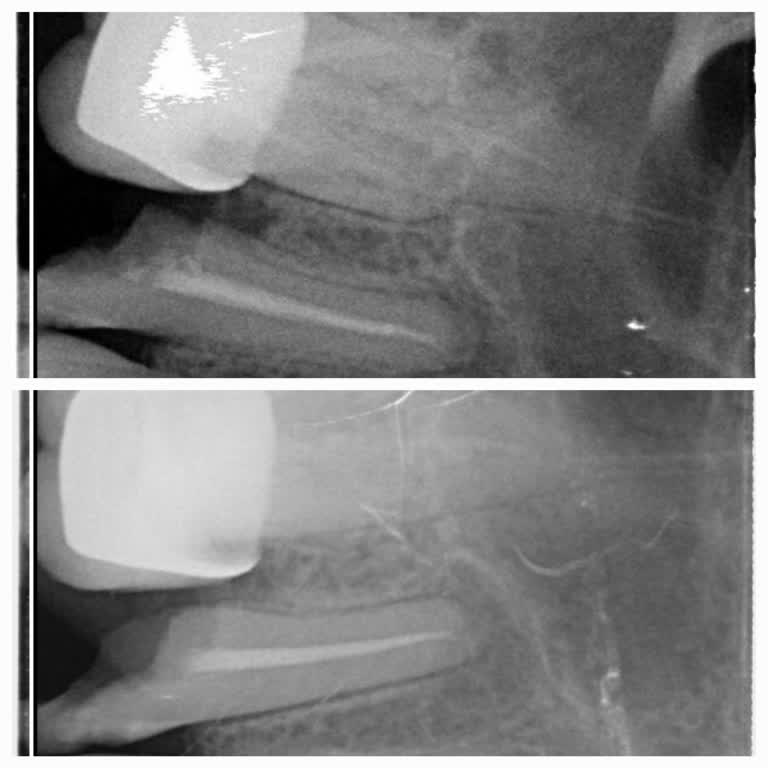

Ataşehir Ağız ve Diş Sağlığı Hastanesi'nde kanal tedavisi olmam gereken dişime 'derin dolgu ile kurtarırız' diyerek derin dolgu yapan Doktor *** nedeniyle sürekli dişimde apse oluşmaya başladı. Kontrole gidip şikayetimi söylediğimde Endodonti bölümüne, yani kanal tedavisi olmam gerektiği söylendi. B...